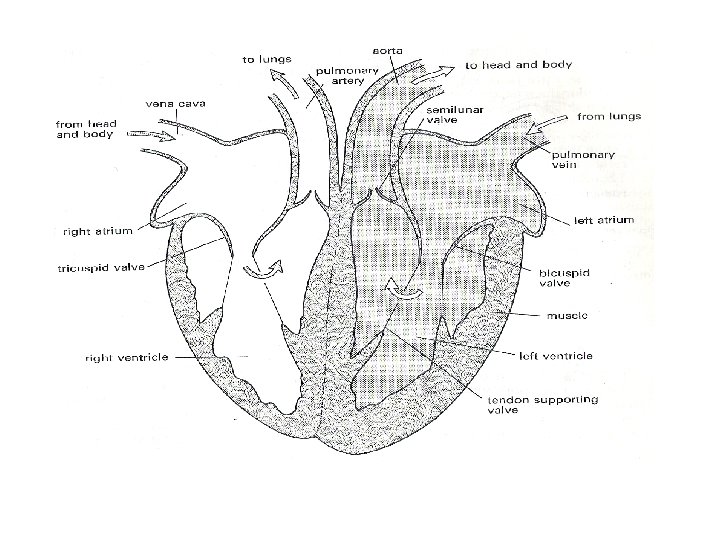

Internal Structure of the Heart • The heart has four chambers: the left and right atria (1 atrium) and the left and right ventricles. • The following diagram is the internal structure of the heart.

• Remember that the left side (RED) accepts and pumps out oxygenated blood. • The right side of the heart (BLUE) accepts and pumps out deoxygenated blood.

VALVES IN THE HEART • There are four valves in the heart: – Two semilunar valves, (one in each side of the heart). – Two atrioventricular valves (one each found between the atria and ventricles on both sides of the heart). – The function of the valves in the heart are to direct the flow of blood in only one direction.

Path of Oxygenated Blood • Pulmonary vein left atrium • Through mitral valve down into the left ventricle. • The ventricle then contracts forcing the mitral valve closed and opening the semilunar valve. • The blood then flows up into the aorta and around the body.

Path of Deoxygenated blood • Vena cava right atrium • Through tricuspid valve right ventricle. • Ventricle contracts, tricuspid valve closes, semilunar valve opens. • Blood flows to the pulmonary artery lungs.